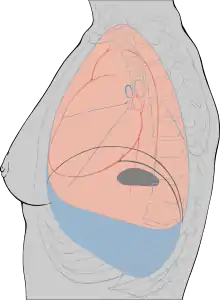

Pleural effusion

In some cases of pleurisy, excess fluid builds up in the pleural space. This is called a pleural effusion. The buildup of excess fluid, will more often than not force the two layers of the pleura apart so they don't rub against each other when breathing. This can relieve the pain of pleurisy. A large amount of fluid can result in collapse of the lung. This can make it difficult to breathe.

A person can develop a pleural effusion in the absence of pleurisy. For example, pneumonia, heart failure, cancer, or a pulmonary embolism can lead to a pleural effusion.

Hemothorax

Blood also can collect in the pleural space. This is called hemothorax. The most common cause is injury to the chest from blunt force or surgery on the heart or chest. Hemothorax also can occur in people with lung or pleural cancer.

Hemothorax can put pressure on the lung and force it to collapse. It also can cause shock, a state of hypoperfusion in which an insufficient amount of blood is able to reach the organs.